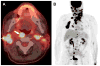

Cross-sectional imaging plays an important role in the evaluation of the retropharyngeal space (RPS) and the prevertebral space (PVS). Because of their deep location within the neck, lesions arising within these spaces are difficult, if not impossible, to evaluate on clinical examination. This article details the cross-sectional anatomy and imaging appearances of primary and secondary diseases involving the RPS and PVS, including metastasis and spread from adjacent spaces. The role of image-guided biopsy is also discussed.